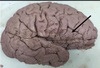

1. Identify the highlighted (red) area. 2. What structure is the black arrow pointing to? 3. What structure is the blue arrow pointing to? 4. What structure is the green arrow pointing to?

1. Occipitotemporal Sulcus 2. Parahippocampal Gyrus/ uncus 3. Medial Occipitotemporal gyrus 4. Lateral Occipitotemporal gyrus